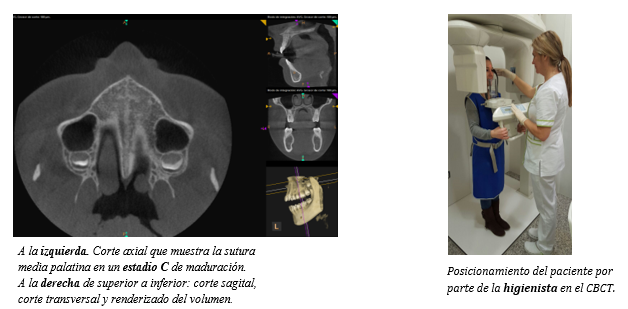

En este caso se decidió realizar una exploración radiográfica del maxilar superior con un equipo de CBCT (Carestream CS9300 Select). La colaboración del higienista es fundamental para la correcta colocación del paciente; en este caso también realizó la exposición al estar legalmente habilitada (operador de radiología dental con acreditación por el Consejo de Seguridad Nuclear). El estudio de las imágenes obtenidas (cortes axiales) realizado por la ortodoncista permitió determinar que la paciente se encontraba en un estadio C de maduración sutural, en base a la clasificación de Angelieri et al.,2013 y 2015 (6 ,7), también ya muy recientemente Bonfim et al., 2016 proponen la posibilidad de valorar la maduración cervical con esta misma prueba (8). En base a ello pudimos determinar que no se había producido el cierre completo de la sutura, lo que permitió optar por la colocación de un disyuntor acrílico de cementado directo y realizar la separación de los segmentos maxilares de manera efectiva.

Una vez finalizada la fase de expansión maxilar, determinada clínicamente por la resolución de la mordida cruzada bilateral y la presencia de un diastema inter-incisivo, se realizó una nueva exploración radiográfica con CBCT para verificar la apertura de la sutura y valorar la integridad del hueso de la cortical vestibular (ausencia de dehiscencia y fenestracción).